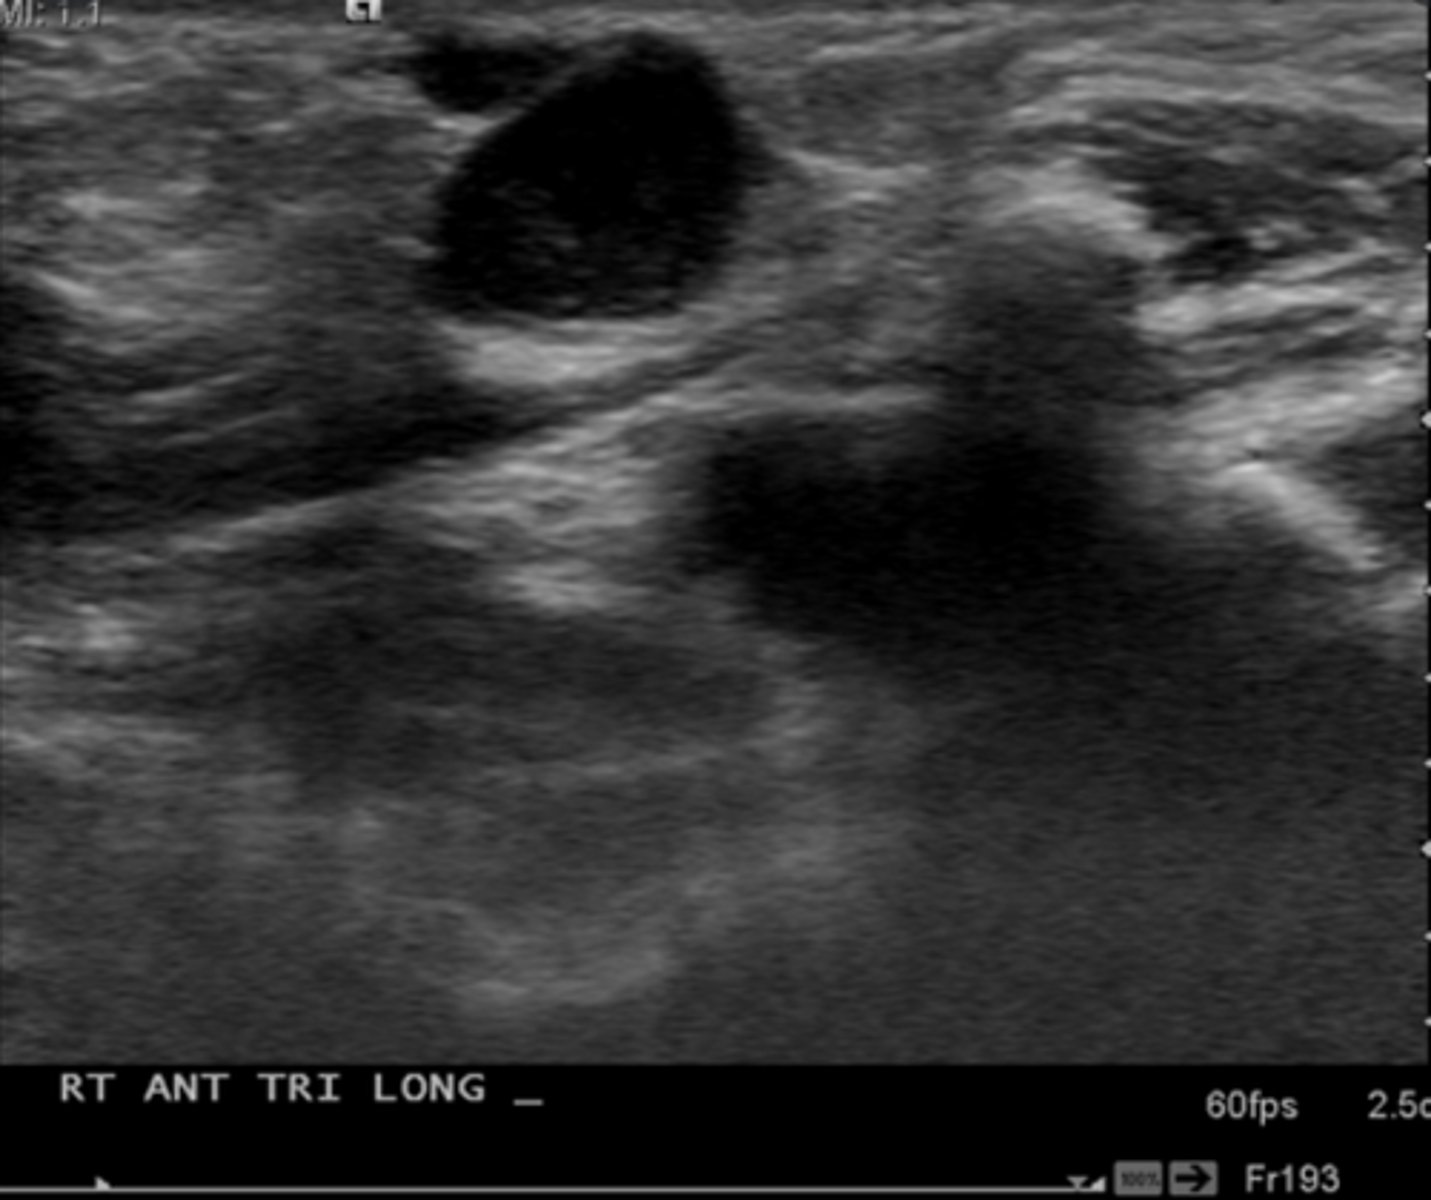

Benign Thyroid Neoplasms - Cyst:

10-15% of solitary thyroid nodules

Etiology

-Simple cyst

Clinical findings

-Asymptomatic

-Palpable neck mass

Sonographicfindings

-Anechoic mass

-Smooth wall margins

-Posterior acoustic enhancement

-May demonstrate internal debris

Parathyroid Pathology - Cyst:

-Uncommon

-_____ prevalence

-_____ yrs of age

Sonographic findings

-_____echoic mass located _____ and ______ to the thyroid gland

-_____ wall margins

-Posterior acoustic _____

-Female prevalence

-60-70 yrs of age

-Anechoic mass located posterior and medial to the thyroid gland